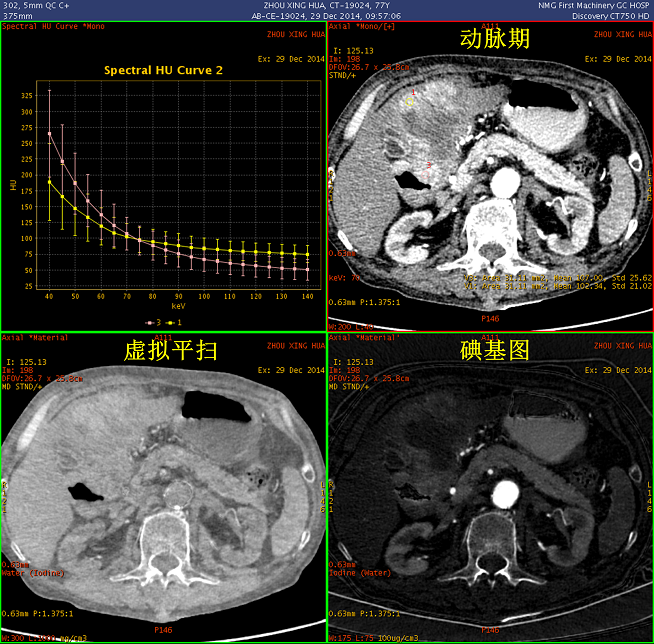

扫描参数 模式:GSI 550mA@0.8sec/rot@DC40mm@SFOV Body Large 螺距:1.375:1 造影剂注射方案 350mgI/100ml@70ml@3.5ml/sec Smartprep/TH120/AutoVoice Off 静脉期设置35s延迟;延迟期设置120s

能谱CT诊断 胃恶性淋巴瘤

观察不同期相显示:胃窦部及十二指肠区团块,碘基图呈高密度证明有强化(白箭); 胃及十二指肠壁呈明显增厚,范围较广,胃及肠腔明显狭窄(碘基图尤为明显); 肝左叶受压明显

病灶内部密度不均,最大径线:7 × 11cm; GSI曲线分析:增厚的胃壁与外凸的部分能谱曲线一致,证明巨大病灶起源于胃; 延迟期观察,对比剂通过未受明显影响,胃壁无明显僵硬

实质期能谱曲线分析,显示病灶与腹腔内正常淋巴结曲线已有区别

三维融合图像清晰显示病灶轮廓:肝动静脉呈“抱球征”,提示横断位图像所见的肝左叶区域的病灶并非肝实质内,而为受压及部分容积效应所致